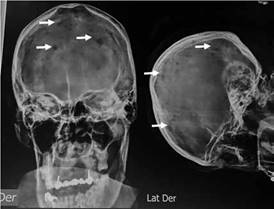

Se realizan radiografías simples de cráneo frontal y perfil las cuales muestran lesiones líticas (Figura 3).

Figura 3 Se observa placa simple de cráneo en proyección anteroposterior y lateral con evidencia de múltiples lesiones líticas en aspecto de cráneo apolillado (flechas).